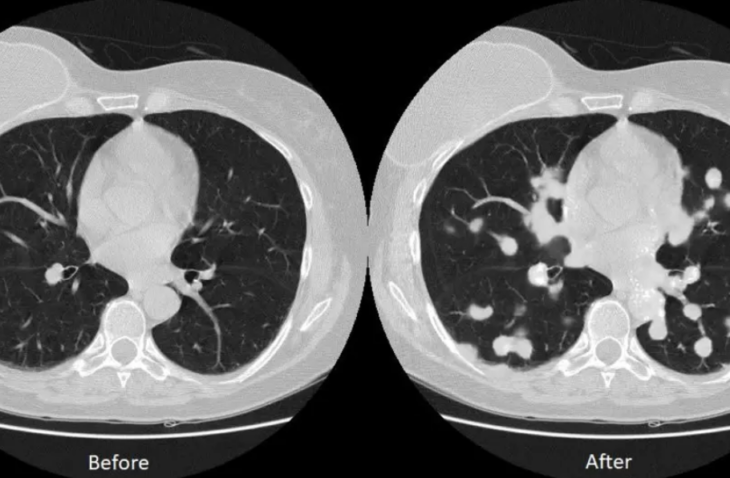

據Medicalxpress上週五報道,莫菲特癌症中心開發了一種分析腫瘤突變並確定治療療程的非侵入性方法,在肺癌的治療方面取得了新的進展。在這種成像方法的幫助下,科學家們能夠精准地地發現異常的葡萄糖代謝,以及準確地描述腫瘤特徵。#以色列新的「非侵入性」癌症治療「靶向並摧毀」 80%的腫瘤細胞